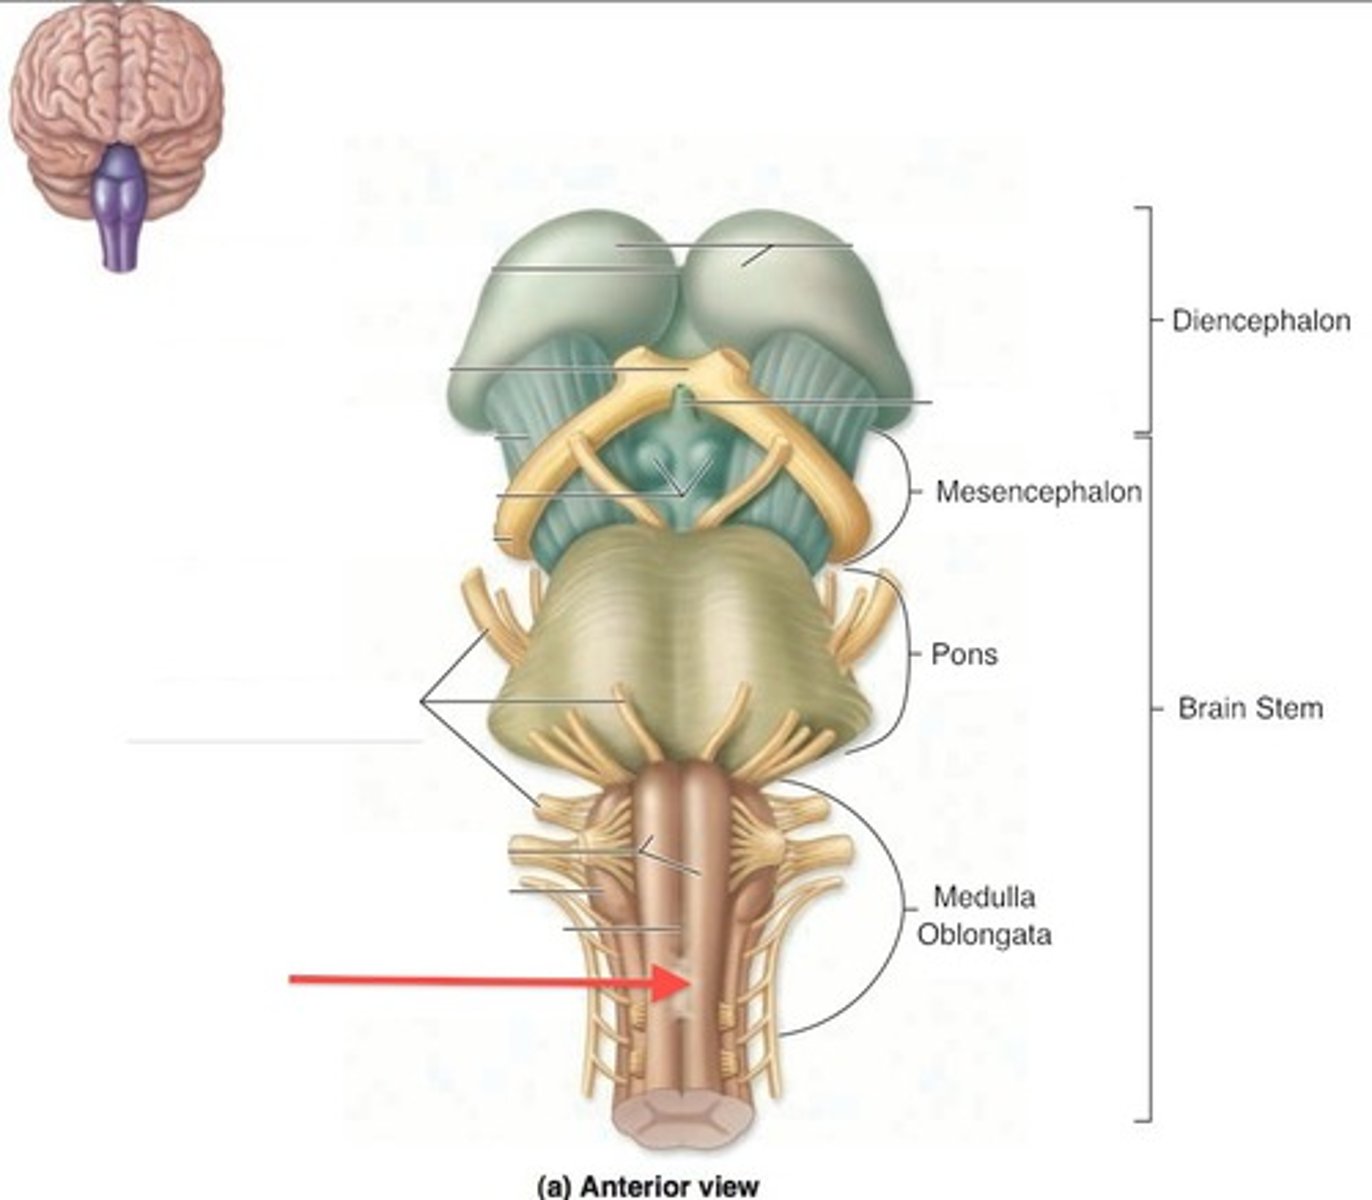

What are the 3 parts of the brain stem?

midbrain, pons, medulla

Which primary brain vesicles is the brain stem derived from?

mesencephalon, rhombencephalon

Which secondary brain vesicles is the brain stem derived from?

mesencephalon, metencephlon, myelencephalon

What is the superior boundary of the medulla?

pontomedullary sulcus

What is the inferior boundary of the medulla?

foramen magnum

What other part of the CNS is the medulla continuous with?

spinal cord

two ridges of tissue on the ventral aspect of the medulla, separated from each other by the ventral median fissure

pyramids

area where most corticospinal fibers decussate over the lower medulla, therefore obscuring the ventral median fissure

pyramidal decussation

elongated mounds of tissue lateral to the medullary pyramids

olives

vertical groove dorsolateral to the inferior olive on each side that gives rise to CN IX and X

postolivary sulcus

name the groove

pontomedullary junction

general portion of the medulla

open medulla

general portion of the medulla

closed medulla

pyramids

ventral median fissure

pyramidal decussation

C